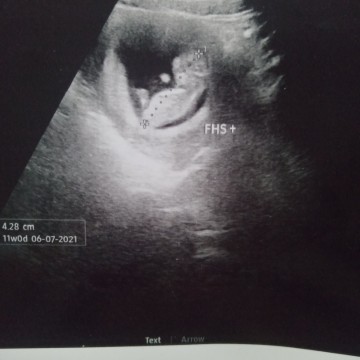

ท้องแรกคะ 👶

หนูได้11สัปดาห์แล้ว บ้านแม่ๆละคะกี่สัปดาห์กันแล้วเอ่ยย❤👶👶